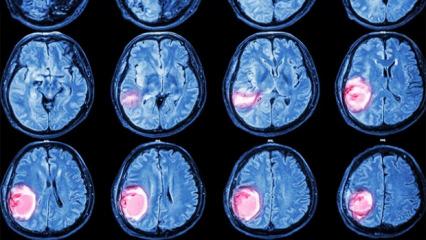

BEYİN YAPISI DEĞİŞİYOR, UYKU DÜZENİ BOZULUYOR

Nöroloji Uzmanı Doç. Dr. Buse Çağla Arı, stresin yalnızca duygusal bir tepki olmadığını, beyin biyolojisini doğrudan etkilediğini belirterek, “Stres bizi tetikleyen, harekete geçiren bir faktördür ancak stres seviyesi arttıkça beynin yapısında değişiklikler oluşabiliyor. Hormon düzeyleri değişiyor, yeni bilgileri öğrenmek zorlaşıyor, başladığımız işleri sürdürmekte güçlük çekebiliyoruz. Kronik stres uyku düzenini bozarak günlük hayatı doğrudan etkiliyor. Uykusuzluk motivasyon kaybı ve zihinsel yorgunluk ortaya çıkarabiliyor. Migren ataklarında artış, diş sıkma ve uyanıklık saatlerinde düzensizlik de kronik stresin sık görülen sonuçları arasında yer alıyor” diye konuştu.